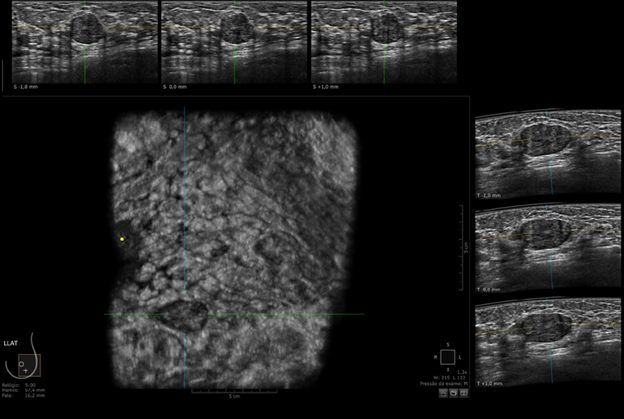

Hình 6. Khối nhỏ sau quầng vú ở vú phải được quan sát rõ trên ABUS (mũi tên vàng) - BIRADS 3

Hình 7. Khối sờ thấy được bên trái được thể hiện rõ trên ABUS.

Ý nghĩa lâm sàng: Nhờ khả năng tái tạo 3D, ABUS giúp bác sĩ quan sát toàn bộ thể tích vú từ nhiều góc độ